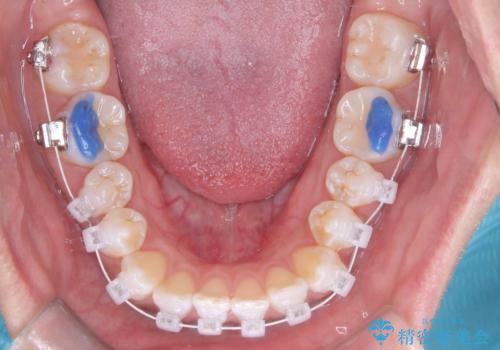

本症例では、治療の途中で**バイトアップ(咬み合わせを一時的に挙上する処置)**を行い、

上下の歯が干渉しない環境を作りながら、捻転や叢生の改善を進めました。

これにより、歯を無理に動かすことなく、効率的かつ安全に歯列を整えることが可能となります。

装置には、ワイヤーに白いコーティングが施された審美性の高いワイヤー矯正装置を使用し、

治療中も目立ちにくい配慮を行いました。